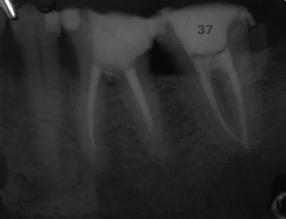

Una corretta terapia canalare con un perfetto sigillo a livello degli apici delle radici è fondamentale. I denti devitalizzati impropriamente possono creare ulteriori problemi che poi andranno a ripercuotersi sulle cure effettuate successivamente come le ricostruzioni e le corone protesiche con conseguente fallimento del piano terapeutico.

Capita spesso di incontrare denti già devitalizzati in maniera impropria che necessitano, seppur asintomatici, di essere ritrattati per evitare che i granulomi infetti visibili radiograficamente si evolvano riassorbendo tutto l’osso sottostante.